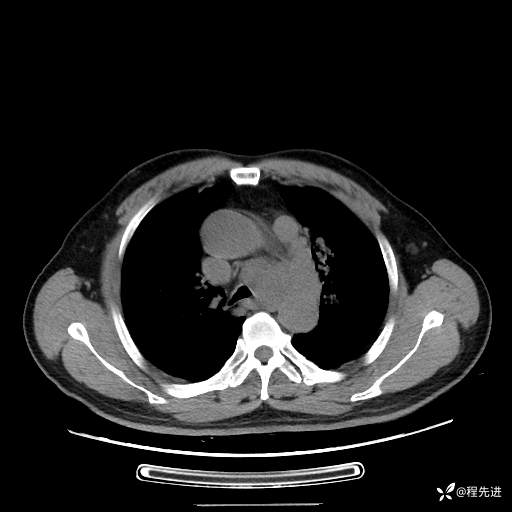

患者性别:男

患者年龄:57岁

简要病史:声嘶2月余

CT平扫+增强: